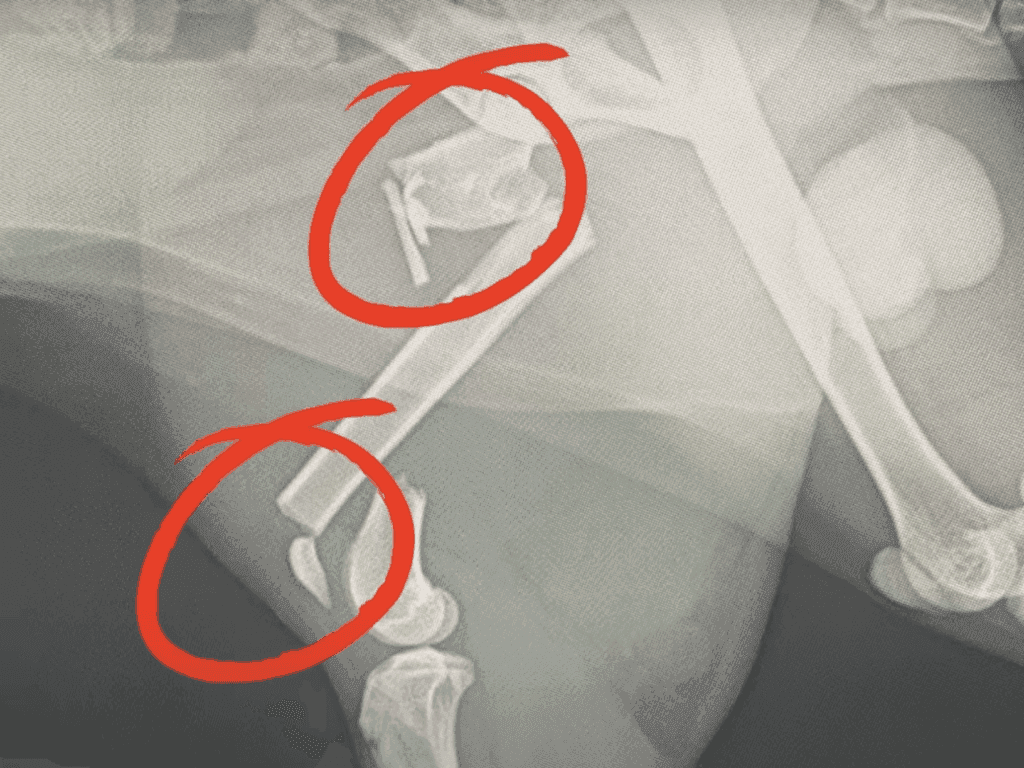

At the clinic, the situation took an even more horrifying turn. The cat wasn’t just injured, it was broken.

X-rays revealed multiple fractures in its legs, leaving the vet stunned at how much pain the tiny creature must have endured.

No wonder it kept twitching uncontrollably. To make things worse, its body had become a breeding ground for insects, with bugs burrowing into its open wounds.

The steel pins in its leg still had to stay for a while, but they weren’t stopping it from running around and getting into mischief.